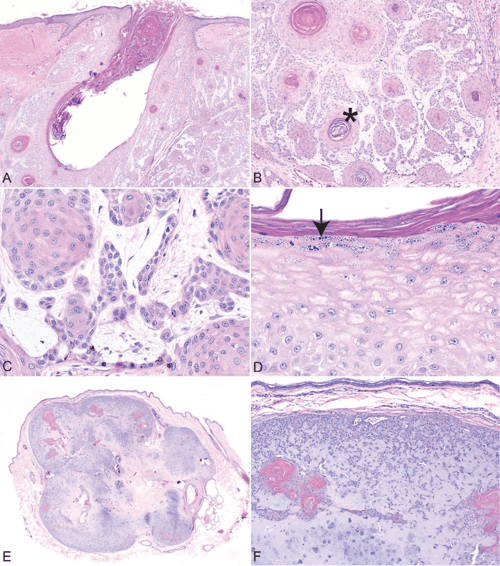

Histologic features of hair follicle neoplasms and cysts in dogs and Hair Follicle Tumor Dog These tumors are mostly benign, but some are malignant and may require additional therapy. This most commonly occurs due to an injury to the area (sometimes on a pressure. Find out which breeds are more prone to these benign or rare malignant skin lumps. Follicular cysts are caused by inflammation or infection at the base of a hair follicle. Learn. Hair Follicle Tumor Dog.

Histologic features of hair follicle neoplasms and cysts in dogs and Hair Follicle Tumor Dog Learn about the five types of skin cancer in dogs, including mast cell tumor, melanoma, squamous cell carcinoma, glandular tumors and hair. This most commonly occurs due to an injury to the area (sometimes on a pressure. These tumors are mostly benign, but some are malignant and may require additional therapy. Find out which breeds are more prone to these. Hair Follicle Tumor Dog.

Hair follicle tumors, dog. Figure 19. Inferior tricholemmoma. The tumor Hair Follicle Tumor Dog Follicular cysts are caused by inflammation or infection at the base of a hair follicle. Learn about the causes, signs, diagnosis, and treatment of sebaceous gland tumors in dogs. They are most common in dogs, less frequent in cats, and rare in other domestic animals. This most commonly occurs due to an injury to the area (sometimes on a pressure.. Hair Follicle Tumor Dog.

Histologic features of hair follicle neoplasms and cysts in dogs and Hair Follicle Tumor Dog They are most common in dogs, less frequent in cats, and rare in other domestic animals. Find out which breeds are more prone to these benign or rare malignant skin lumps. This most commonly occurs due to an injury to the area (sometimes on a pressure. Learn about different types of hair follicle tumors in dogs, such as trichoepithelioma, and. Hair Follicle Tumor Dog.

Histologic features of hair follicle neoplasms and cysts in dogs and Hair Follicle Tumor Dog Follicular cysts are caused by inflammation or infection at the base of a hair follicle. These tumors are mostly benign, but some are malignant and may require additional therapy. This most commonly occurs due to an injury to the area (sometimes on a pressure. Learn about the five types of skin cancer in dogs, including mast cell tumor, melanoma, squamous. Hair Follicle Tumor Dog.

Histologic features of hair follicle neoplasms and cysts in dogs and Hair Follicle Tumor Dog Follicular cysts are caused by inflammation or infection at the base of a hair follicle. Learn about different types of hair follicle tumors in dogs, such as trichoepithelioma, and how to recognize and treat them. These tumors are mostly benign, but some are malignant and may require additional therapy. This most commonly occurs due to an injury to the area. Hair Follicle Tumor Dog.